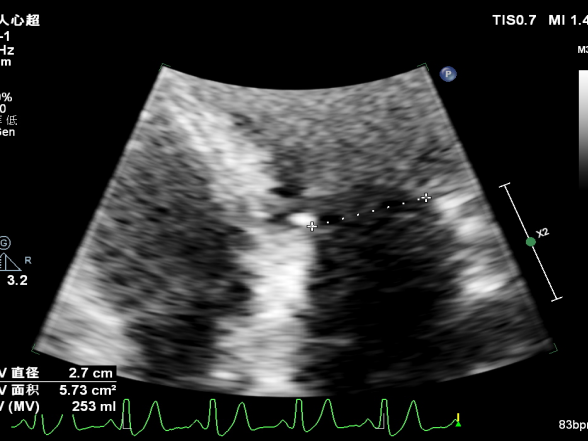

二尖瓣瓣环前后径28mm,左右径27mm

二尖瓣口平均跨瓣压差:6mmHg

夹子放置后二尖瓣口平均跨瓣压差:5mmHg(主要受容量影响,存在高估)

二尖瓣瓣口平均跨瓣压差:5mmHg